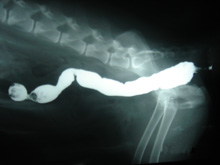

直腸憩室

直腸憩室は、直腸の筋膜の断裂により、直腸に粘膜の袋ができてしまう病気です。

袋にウンチが溜まり排便痛や排便障害を引き起こします。袋が破れた時は、腹腔内にウンチが出てしまい、いろいろな疾患を引き起こしてしまいます。

今回は直腸引き抜き術(正常な直腸まで腸をはがし、引き抜き、肛門にぬいあわせる)を実施し、予後が改善された症例です。